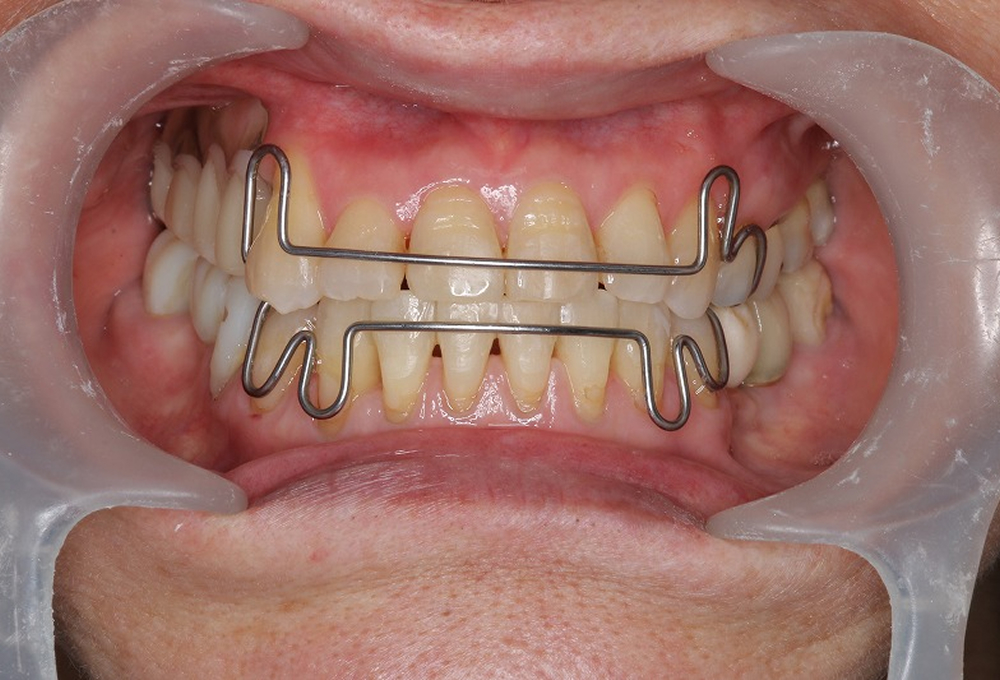

④矯正中